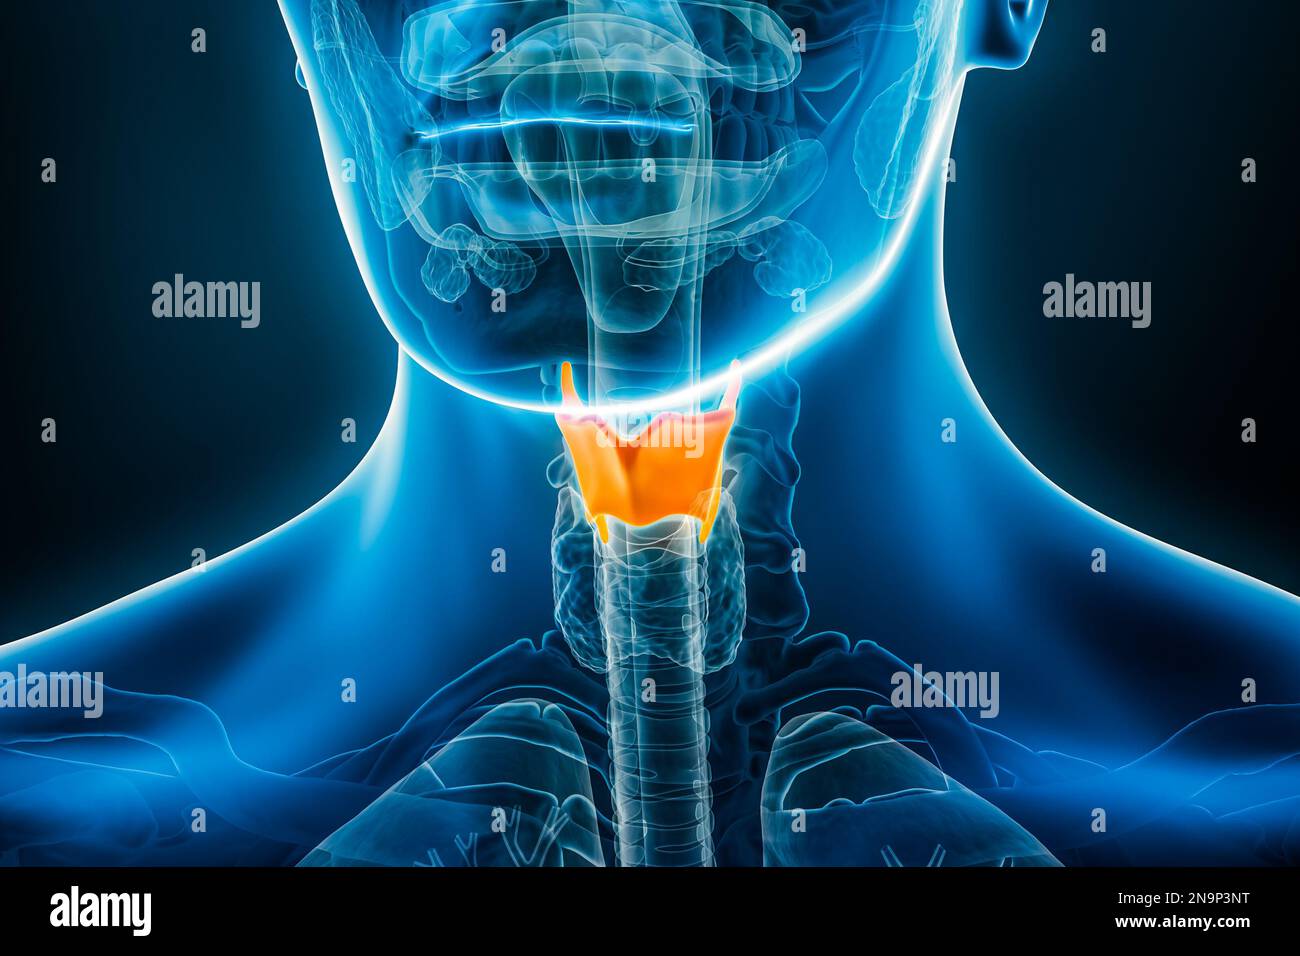

RF2N9P3NT–Röntgen des Schilddrüsenknorpels 3D-Darstellung mit männlichen Körperkonturen. Menschliche Anatomie, Medizin, Biologie, Wissenschaft, Gesundheitskonzepte.